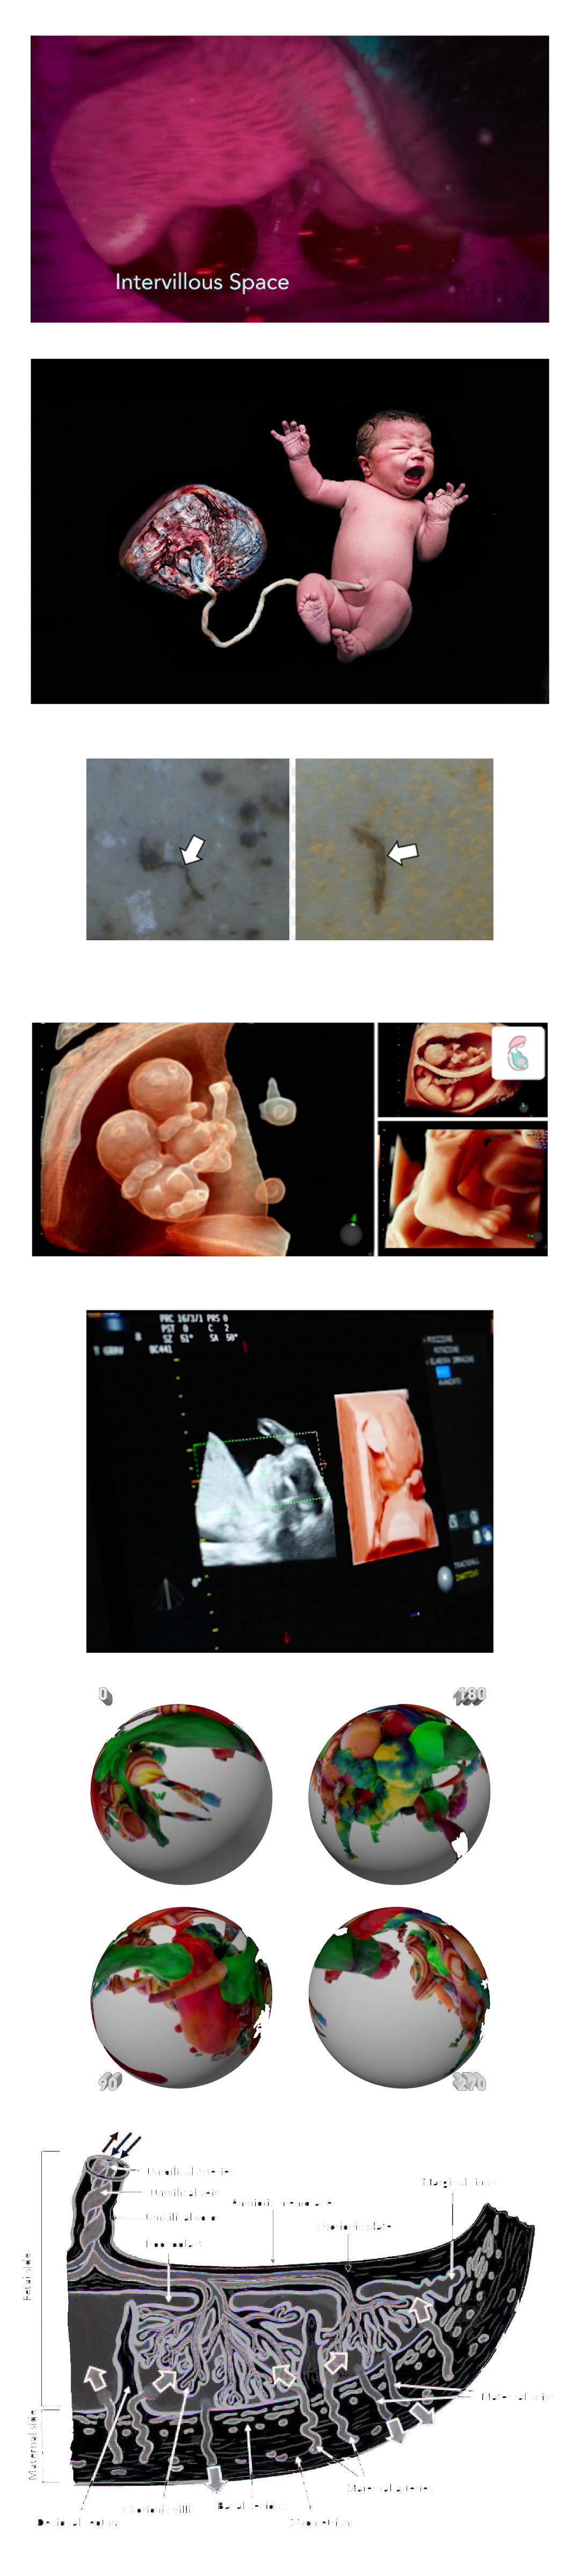

MICROPLASTICS (MPS) ARE DEFINED AS PLASTIC PARTICLES SMALLER THAN 5 MM. THEY HAVE BEEN FOUND ALMOST EVERYWHERE THEY HAVE BEEN SEARCHED FOR AND RECENT DISCOVERIES HAVE ALSO DEMONSTRATED THEIR PRESENCE IN HUMAN PLACENTA, BLOOD, MECONIUM, AND BREASTMILK, BUT THEIR LOCATION AND TOXICITY TO HUMANS HAVE NOT BEEN REPORTED TO DATE. THE AIM OF THIS STUDY WAS TWOFOLD:

1. TO LOCATE MPS WITHIN THE INTRA/EXTRACELLULAR COMPARTMENT IN HUMAN PLACENTA.

2. TO UNDERSTAND WHETHER THEIR PRESENCE AND LOCATION ARE ASSOCIATED WITH POSSIBLE STRUCTURAL CHANGES OF CELL ORGANELLES. USING VARIABLE PRESSURE SCANNING ELECTRON MICROSCOPY AND TRANSMISSION ELECTRON MICROSCOPY, MPS HAVE BEEN LOCALIZED IN TEN HUMAN PLACENTAS. IN THIS STUDY, WE DEMONSTRATED FOR THE FIRST TIME THE PRESENCE AND LOCALIZATION IN THE CELLULAR COMPARTMENT OF FRAGMENTS COMPATIBLE WITH MPS IN THE HUMAN PLACENTA AND WE HYPOTHESIZED A POSSIBLE CORRELATION BETWEEN THEIR PRESENCE AND IMPORTANT ULTRASTRUCTURAL ALTERATIONS OF SOME INTRACYTOPLASMIC ORGANELLES (MITOCHONDRIA AND ENDOPLASMIC RETICULUM). THESE ALTERATIONS HAVE NEVER BEEN REPORTED IN NORMAL HEALTHY TERM PREGNANCIES UNTIL TODAY. THEY COULD BE THE RESULT OF A PROLONGED ATTEMPT TO REMOVE AND DESTROY THE PLASTIC PARTICLES INSIDE THE PLACENTAL TISSUE. THE PRESENCE OF VIRTUALLY INDESTRUCTIBLE PARTICLES IN TERM HUMAN PLACENTA COULD CONTRIBUTE TO THE ACTIVATION OF PATHOLOGICAL TRAITS, SUCH AS OXIDATIVE STRESS, APOPTOSIS, AND INFLAMMATION, CHARACTERISTIC OF METABOLIC DISORDERS UNDERLYING OBESITY, DIABETES, AND METABOLIC SYNDROME AND PARTIALLY ACCOUNTING FOR THE RECENT EPIDEMIC OF NON-COMMUNICABLE DISEASES.